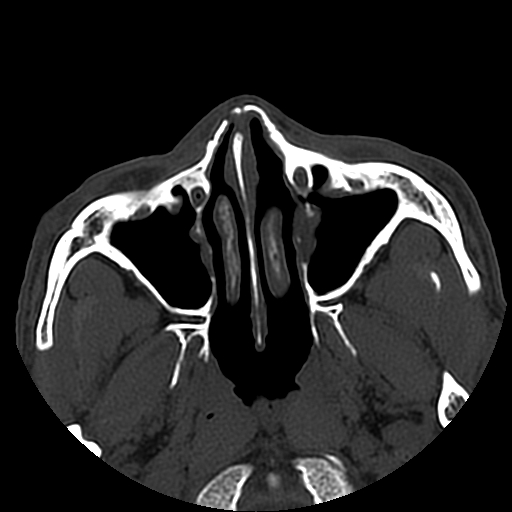

以下是引用liaoqiang在2008-7-16 21:15:00的发言:[br]右侧鼻骨骨折

以下是引用zxd95在2008-7-16 21:39:00的发言:[br]右侧上颌骨额突骨折。[br][br][br][br]